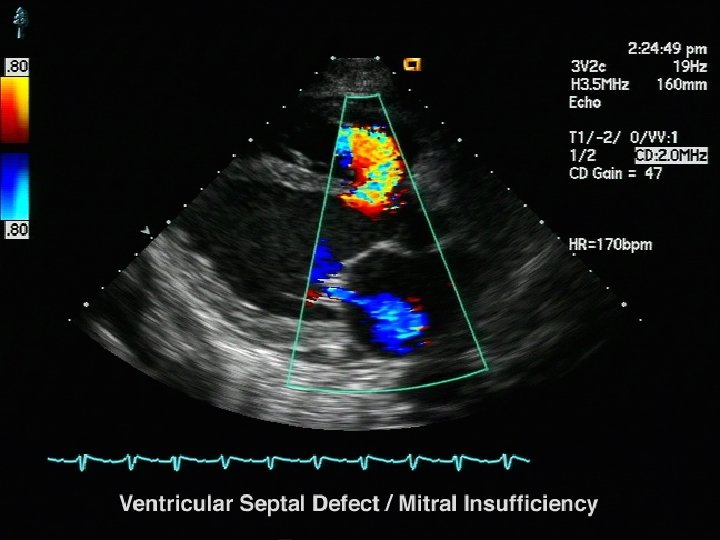

Insuficiencia Mitral • La presion en la auricula izquierda esta elevada • Hipertension puulmonar y los sintomas son de insduficiencia cardiaca • La IM moderada a severa esta presente cuando el 50% o 0 mas de la eyeccion del ventriculo izquierdo regurgita a auricula izquierda. • En agudos , pequeña regurgitacion puede causar severa congestion pulmonar porque la AI no le da tiempo a ser complaciente • No toleran el incremento de la resistencia vascular sistemica porque estos cambios agudos aumentan la regurgitacion mitral. • La FC debe estar normal o ligeramente aumentada, excepto en pacientes con cardiopatia isquemica. • Tolera moderadomente la disminicion de la contractilidad, y es beneficioso sobretodo si esta presente la cardiopatia isquemica.

Importante Los pacientes con IM son sensibles a cambios en la RVS. El aumento de la RVS aumenta el factor de regurgitacion en la insuficiencia mitral, baja el volumen con caida de la presion arterial, en cambio la disminucion de la RVS disminuye el factor regurgitante, aumenta el volumen minuto y cionsecuentemente la presion arterial. La disminucion de la Fc produce sobr 4 ecarga aguda de volumen en la AI. En cambio ligero aumento de la FC aumenta el volumen minuto.

La fisiopatologia en agudo • • Aumento de la presion AI Disminucion de VM Disminucion de la PAM Aumento de la fc Aumento de la contractilidad Aumento volumen diastolico del VI Aumento de la presion de fin de diastole del VI • Aumento de la demanda de oxigeno

La fisiopatologia en cronico • El aumento de volumen dela AI lleva a FA, edema pulmonar y falla VD • La sobrecarga volumetrica del VI lleva a hipertrofia VI, caida del VM y falla VD

Objetivos Hemodinamicos • • • FC 80 – 95 Ritmo estable Precarga no modificada, ligeramente aumentada RVS disminuida RVP abolir su aumento Contractilidad mantenida, ligeramente disminuida